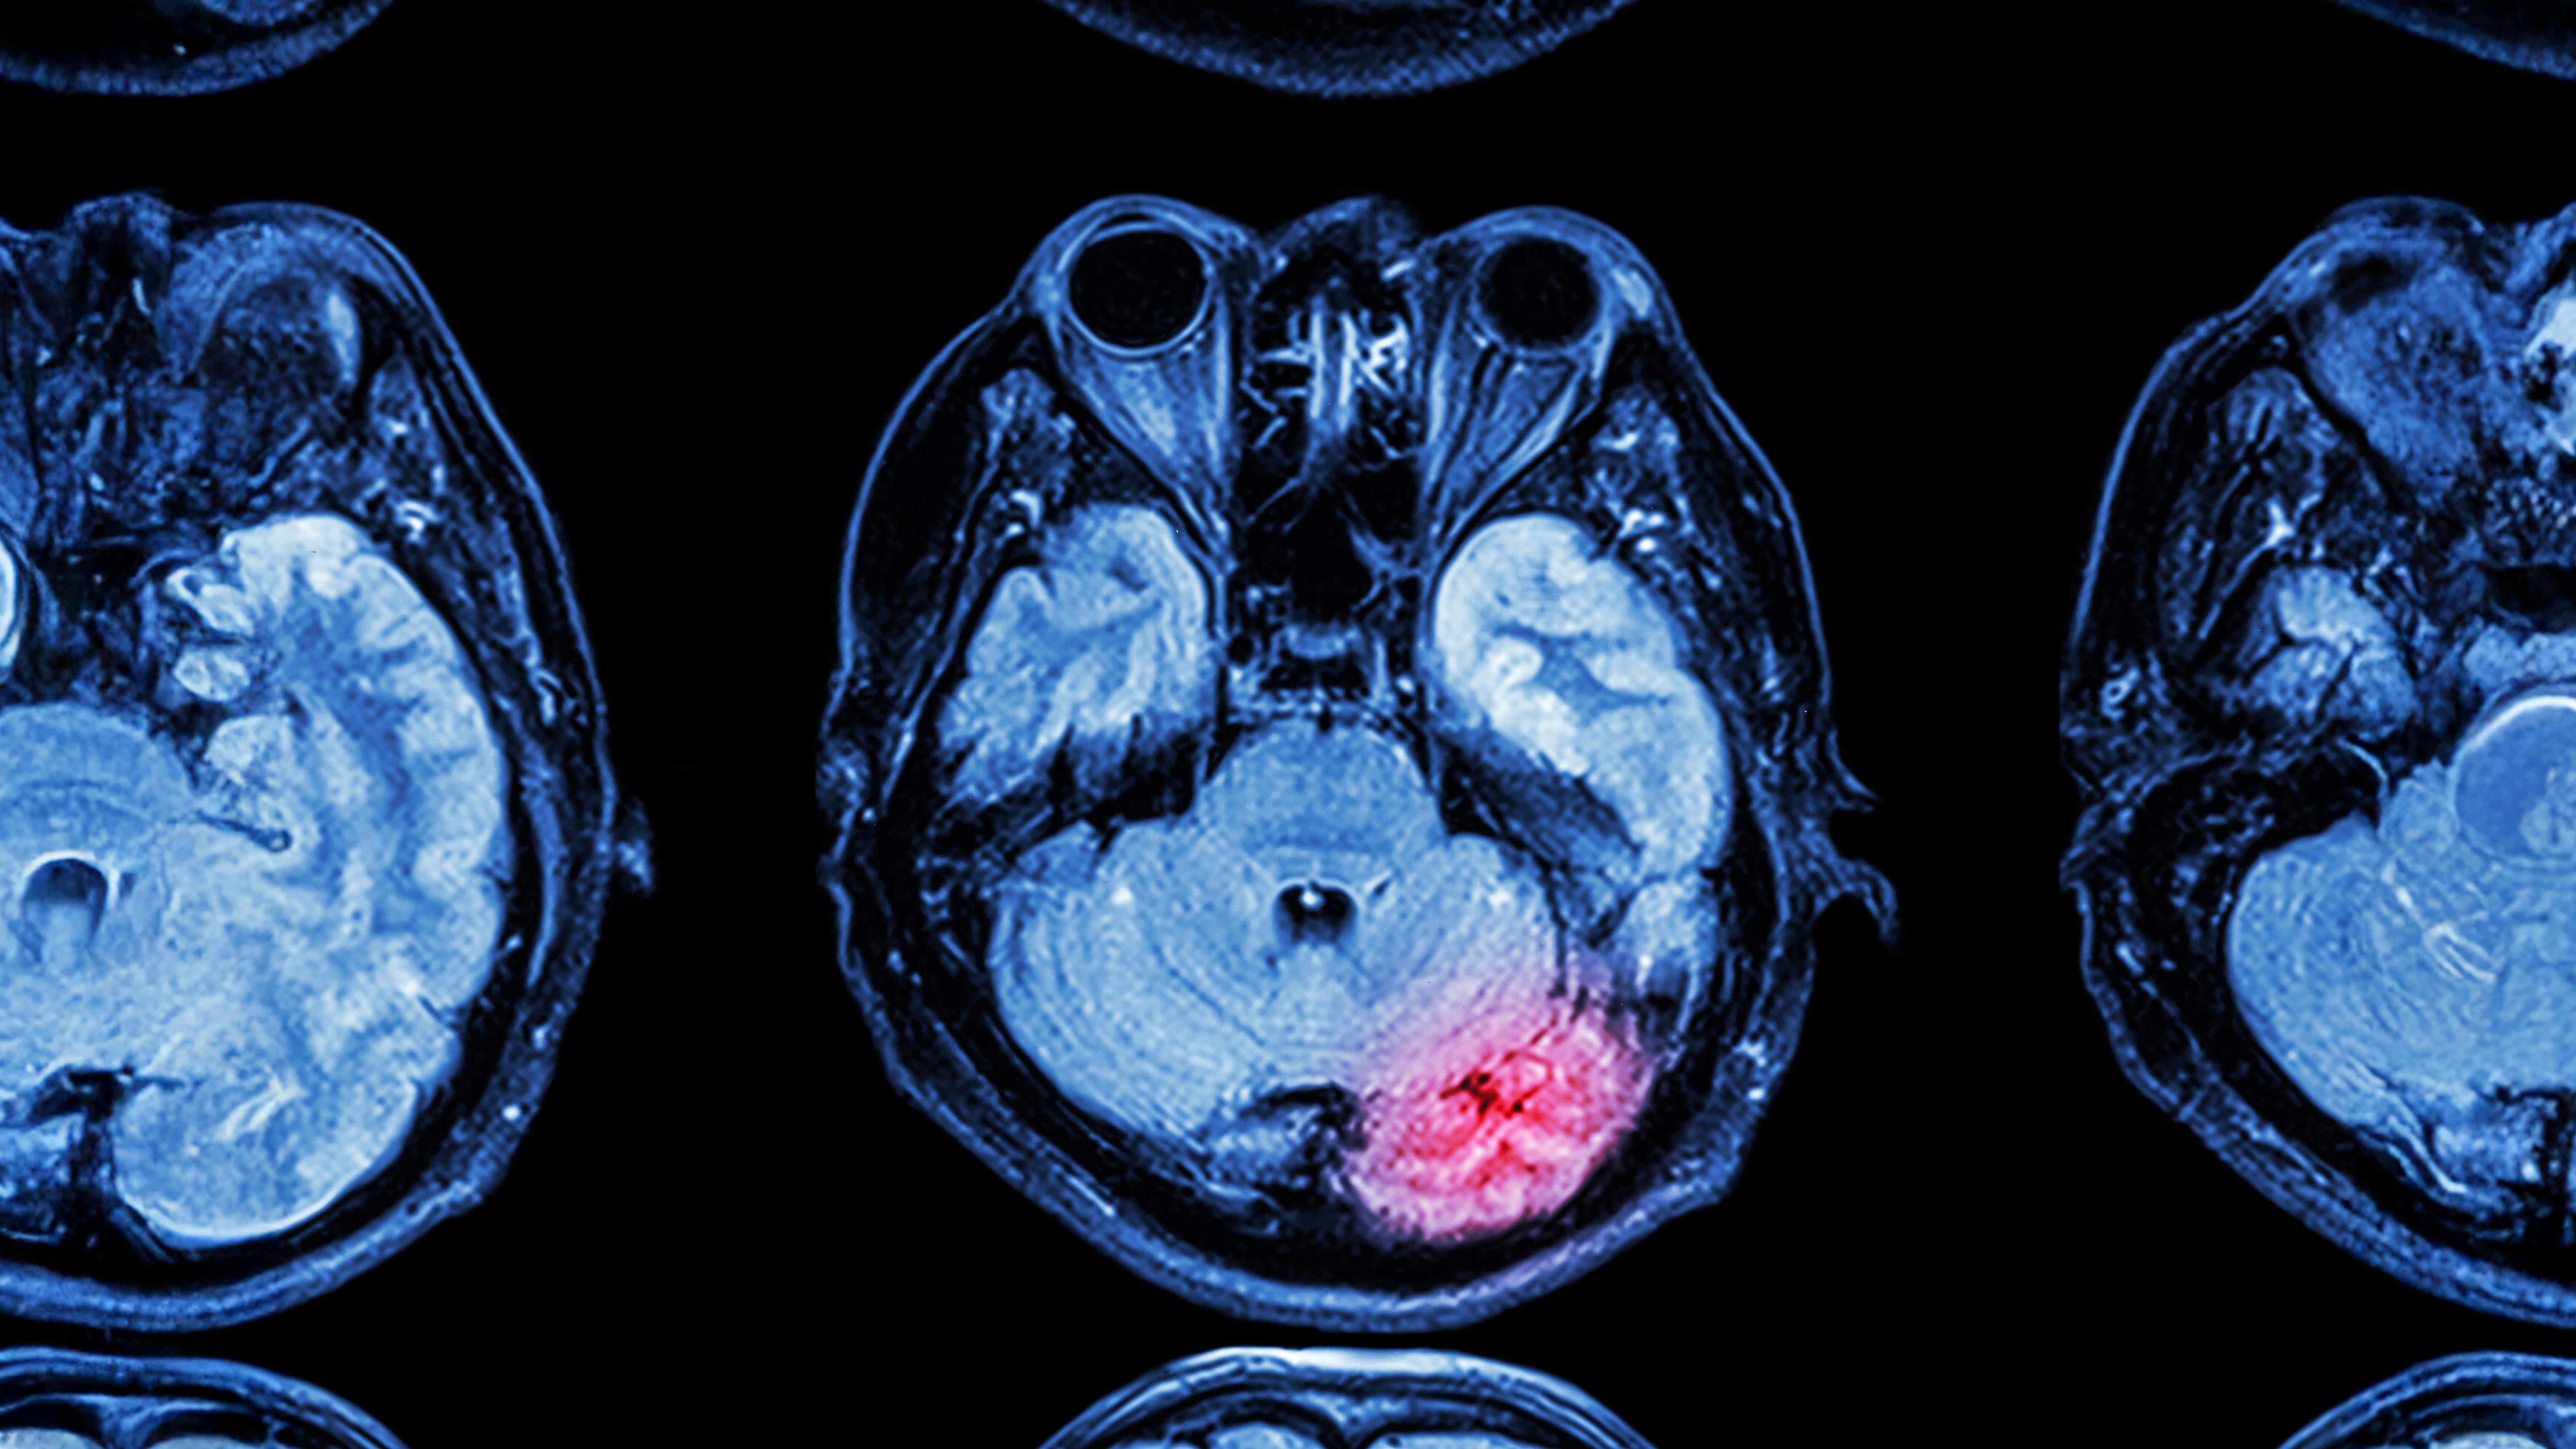

Curix’s technology is designed to advance microbubble-enhanced FUS for blood-brain barrier modulation (FUS-BBB) by offering improvements of current state-of-the-art methods. These methods utilize polydisperse microbubbles administered through manual bolus injection or gravity drip infusion. Our goal is to make FUS-BBB more clinically accessible by standardizing protocols and improving treatments for brain disease.

1) Initial clinical applications are anticipated in neuro-oncology, focusing on patients suffering from recurrent glioblastoma, as well as for the treatment of neurodegenerative diseases such as Parkinson’s disease and Alzheimer’s disease.